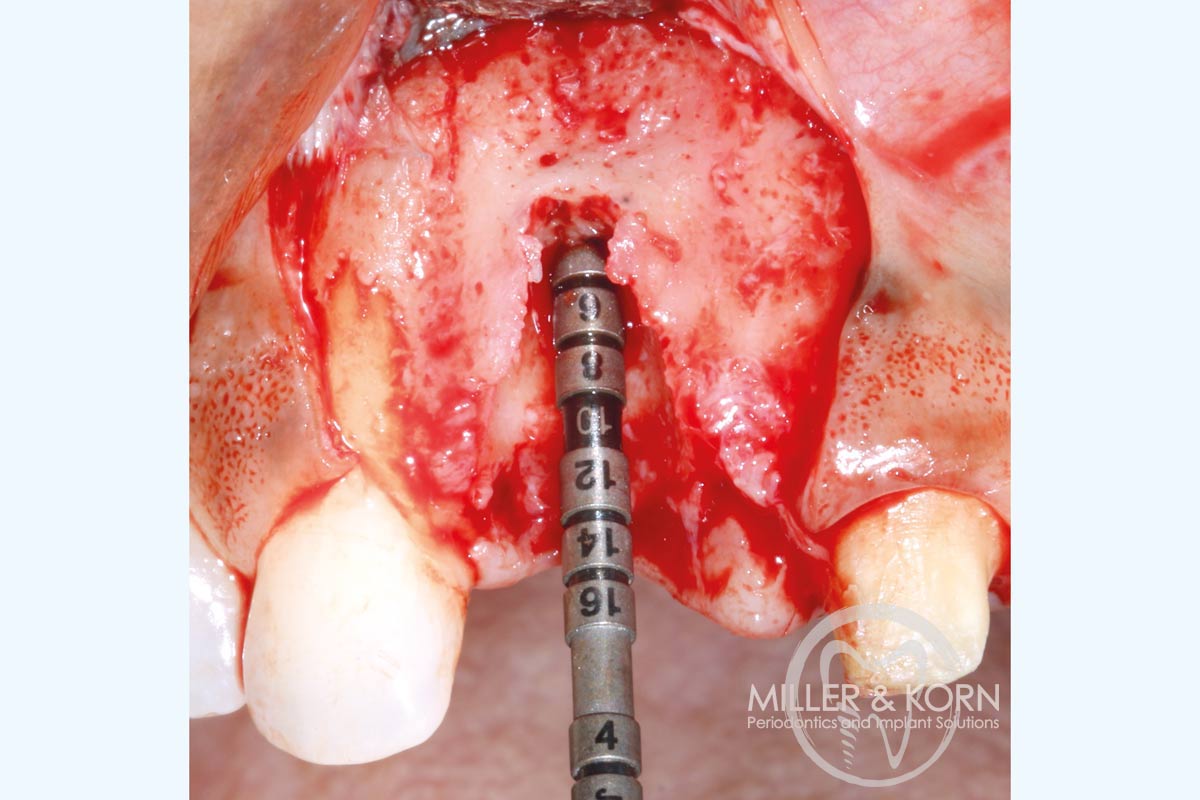

5/22 - Implant direction indicator.Immediate implant placement and regeneration of ridge using an allograft bone ring and Jason® membrane - Drs. Miller and Korn